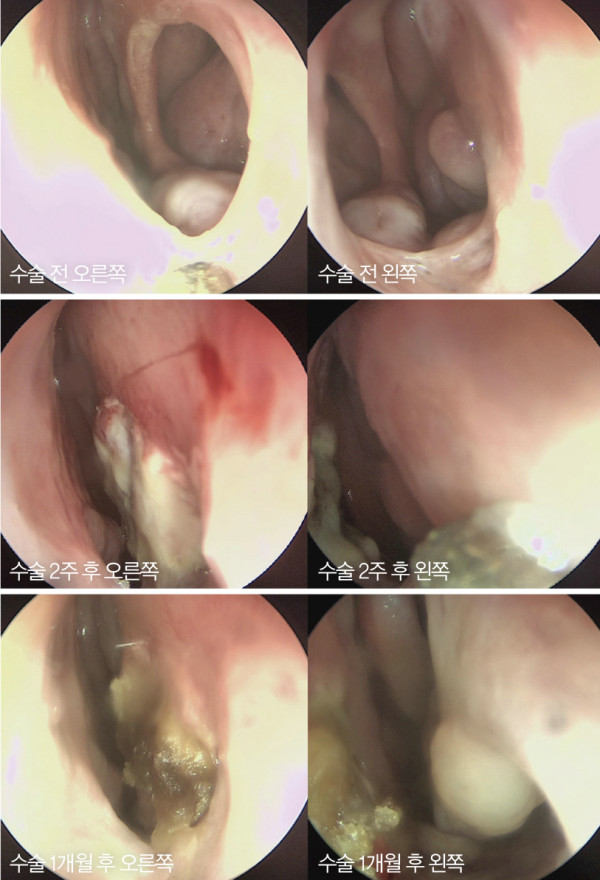

그림 5. 수술 전과 수술 2주 후, 그리고 수술 1개월 후 내시경상 사진. 천공

주변에 점막이 자라 들어와 천공 사이즈가 매우 줄었다. 뒤쪽에 작은 사이즈의

천공이 남아 있다

수술 약 1주 후 실라스틱 판을 제거하였다. 수술 2주 후 와 4주 후 내시경상 천공 주변에 점막이 자라 들어와 천공이 막힌 것을 관찰할 수 있었다

수술 약 1주 후 실라스틱 판을 제거하였다. 수술 2주 후 와 4주 후 내시경상 천공 주변에 점막이 자라 들어와 천공이 막힌 것을 관찰할 수 있었다. 수술 후 비출혈 통증, 휘파람 소리 등의 증상이 개선되었으며 코막힘 증상 또한 개선되었다. 수술 1개월 후 CT 확인 결과 비중격 천공이 대부분 막혔으나 뒤쪽에 4㎜×5㎜ 사이즈의 미세천공이 남았다. 비중격 천공 사이즈가 매우 크고 원형이며, 중간 부위에 위치하는 등 복합적 인 이유

때문이다